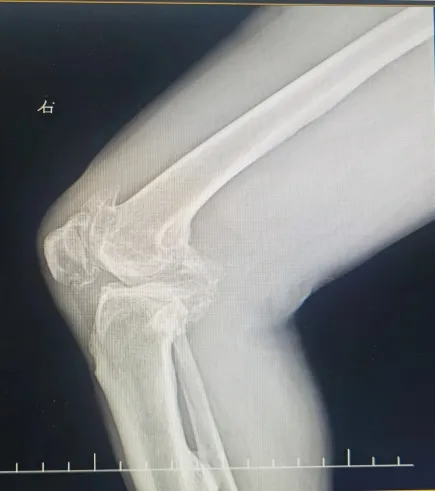

今年68岁的何爷爷是一位典型的右膝重度骨关节病患者。他右膝内翻畸形严重,行走时存在明显的跛行现象及O型腿,膝关节屈伸角度受限,下蹲困难,内侧胫骨平台缺损多,下肢力线极差,手术难度极大。多年来他饱受右膝疼痛的折磨,尤其在上下楼梯或长时间站立时,疼痛感更是明显加剧。